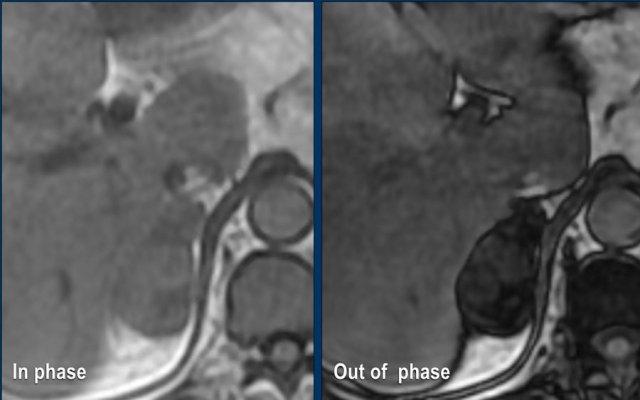

MRI chuỗi xung đảo pha (Out-of-phase imaging)

U tuyến nghèo lipid cũng có thể được chẩn đoán bằng chuỗi xung đảo pha.

Các u này chứa đủ lượng mỡ vi thể để gây ra sự giảm tín hiệu trên ảnh đảo pha so với ảnh đồng pha, do xảo ảnh dịch chuyển hóa học.

Đây là hình ảnh của bệnh nhân nữ 65 tuổi, phát hiện tình cờ khối tuyến thượng thận phải trên siêu âm ổ bụng được thực hiện vì sỏi thận.

Sự hiện diện của mỡ vi thể được chứng minh bởi sự giảm tín hiệu trên ảnh đảo pha.

Bệnh nhân được theo dõi trong 2 năm do tổn thương hơi không đồng nhất và có kích thước 5,2 cm.

Tổn thương không thay đổi kích thước và không có hoạt động nội tiết.

Tổn thương được chẩn đoán là u tuyến nghèo lipid.